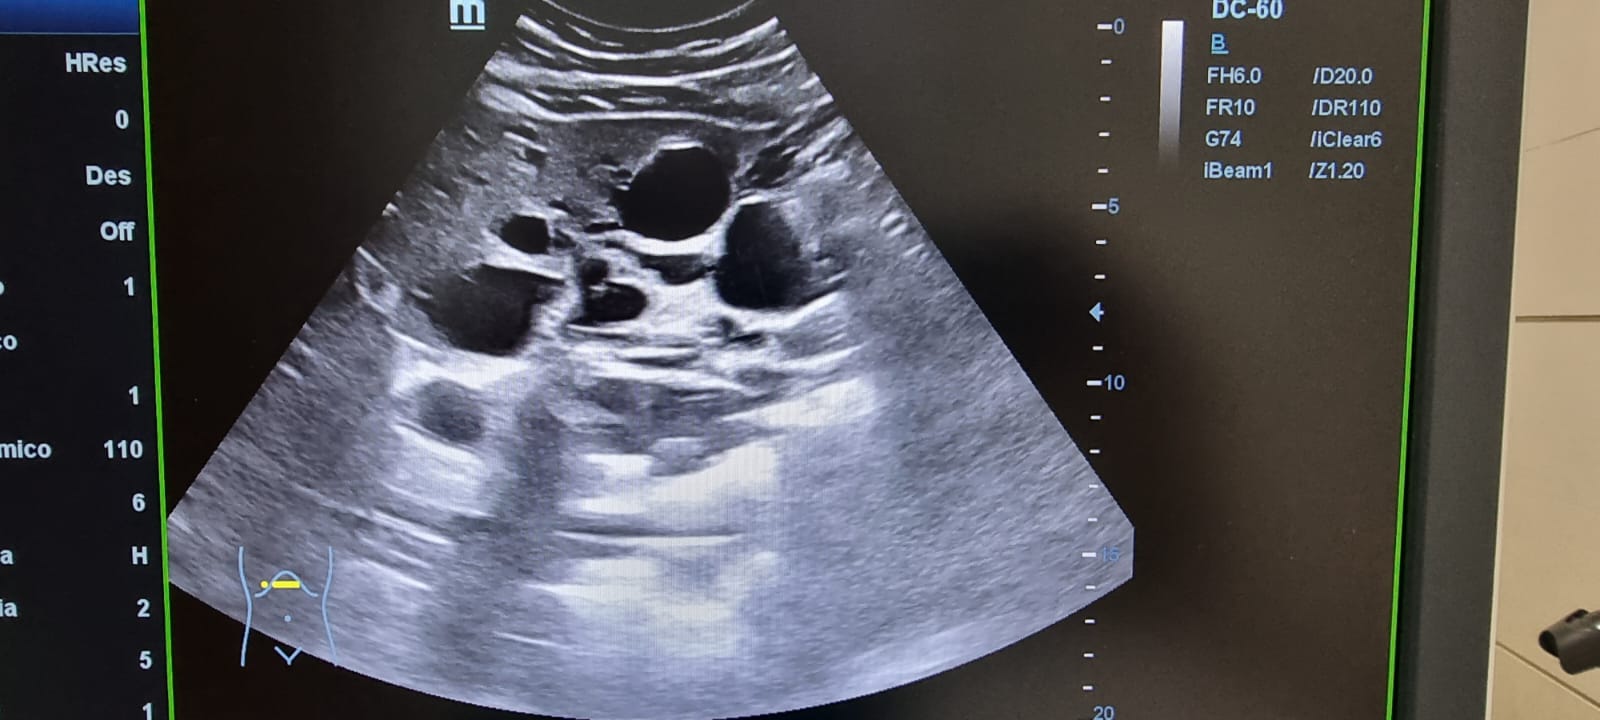

Ecografía abdominal: Hepatomegalia esteatósica difusa leve con múltiples imágenes anecoicas con refuerzo posterior, sin vascularización, compatible con poliquistosis. Riñón derecho con múltiples imágenes anecoicas en polo superior e inferior con refuerzo posterior. Sin signos de uropatía obstructiva. Riñón izquierdo con presencia de múltiples imágenes anecoicas compatibles con poliquistosis.